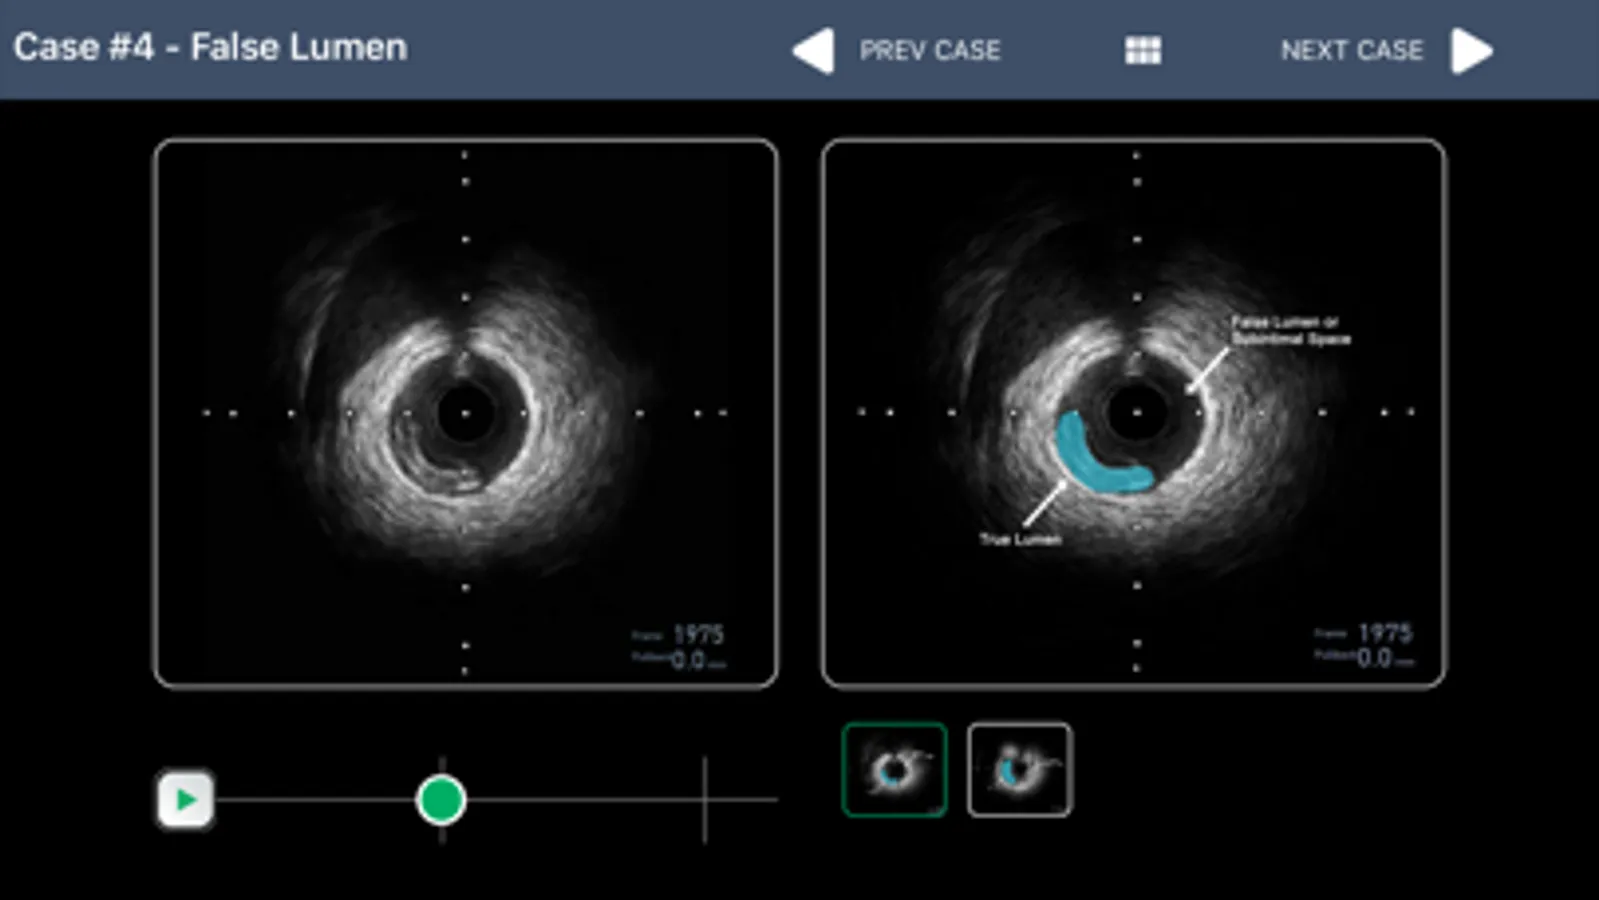

• IVUS image and FFR waveform interpretation guide with questions

• IVUS video clips with image interpretation guide